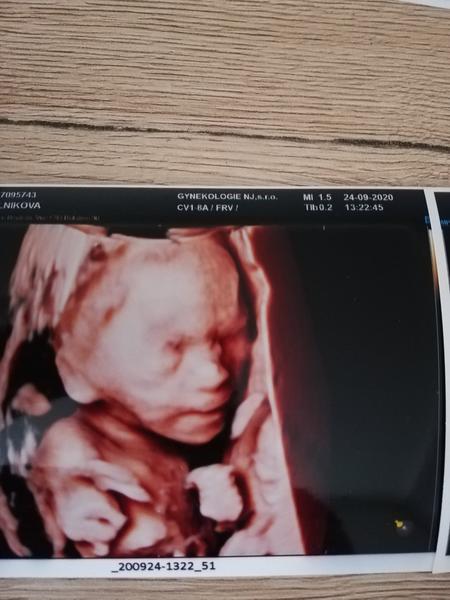

Je to holčička nebo chlapeček? Foto ultrazvuku

Ahoj maminky a budoucí maminky 😉 Prosím, poradila byste mi některá, co vidíte na fotce z ultrazvuku ve 20. týdnu za pohlaví? Určitě jste foteček viděly už mraky, proto vás žádám o radu...Nechci nikoho ovlivnit, proto svůj tip řeknu později 🙂 Děkuju moc!!!

@pavlinkadv na této fotce nevidím pohlavní hrbolek, jiné foto?

@pavlinkadv Ta moje fotka je z 21. týdne a pohlaví tam je 😉